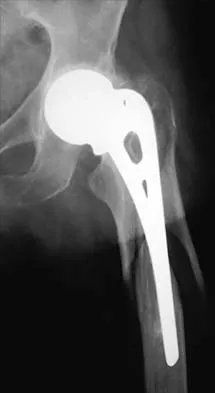

Question 503High Yield

Which of the following best describes the resultant forces on an increased offset stem when compared with a standard offset stem?

Explanation

The increased emphasis on restoring offset in total hip arthroplasty has implications for the forces applied to the components and the fixation interfaces. Static analysis has shown that with an increased affect, joint reaction force on the articulation is decreased. When the resultant load on the hip is "out of plane" (ie, directed anterior to posterior), there is increased torsion where the stem is turned into more retroversion. Buckwalter JA, Einhorn TA, Simon SR (eds): Orthopaedic Basic Science, ed 2. Rosemont, IL, American Academy of Orthopaedic Surgeons, 2000, pp 134-180. Hurwitz DE, Andriaacchi TP: Biomechanics of the hip, in Callaghan J, Rosenberg AG, Rubash HE (eds): The Adult Hip. Philadelphia, PA, Lippincott-Raven , 1998.